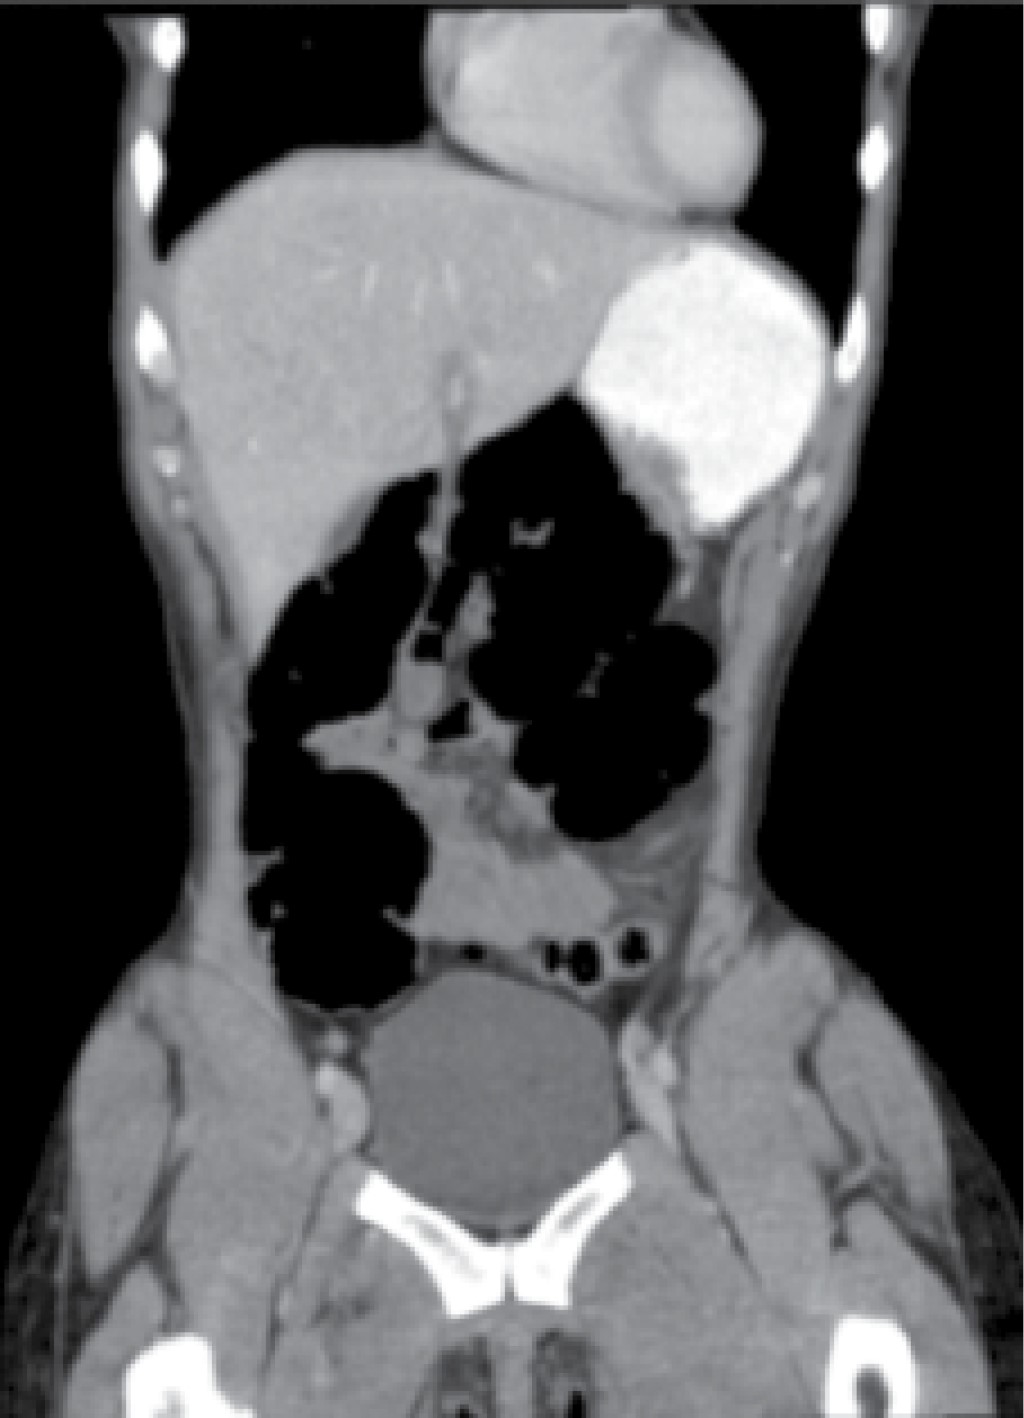

A su ingreso, se tomaron laboratorios los cuales fueron reportados dentro de parámetros normales. Se le practicó un ultrasonido hepático y de vía biliar, en el que no se encontraron alteraciones. A continuación se realizó TAC simple de abdomen donde se reportó una disposición anómala de asas de yeyuno (Figura 1), con situación posterior al estómago, y desplazamiento del colon descendente hacia medial, sin datos de isquemia o perforación, se concluyó estudio como probable hernia interna.

Figura 1